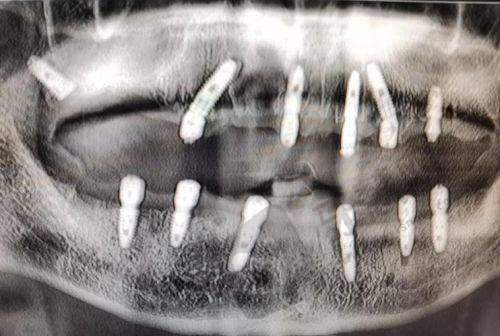

马方医生是北京维尔口腔(惠新东桥分院)的专精口腔种植主治医师。他熟练掌握各类取骨植骨种植手术、上颌窦内/外提升种植手术、软组织移植种植、牙槽骨重度萎缩植骨后种植牙等技术。凭借扎实的理论基础和丰富的临床经验,马方医生能够精细判断患者的口腔状况,为患者制定个性化的种植方案。众多患者在他的治疗下解决了牙齿缺失问题,修复了口腔功能和美观,患者对他的专精技术和负责态度高度认可。